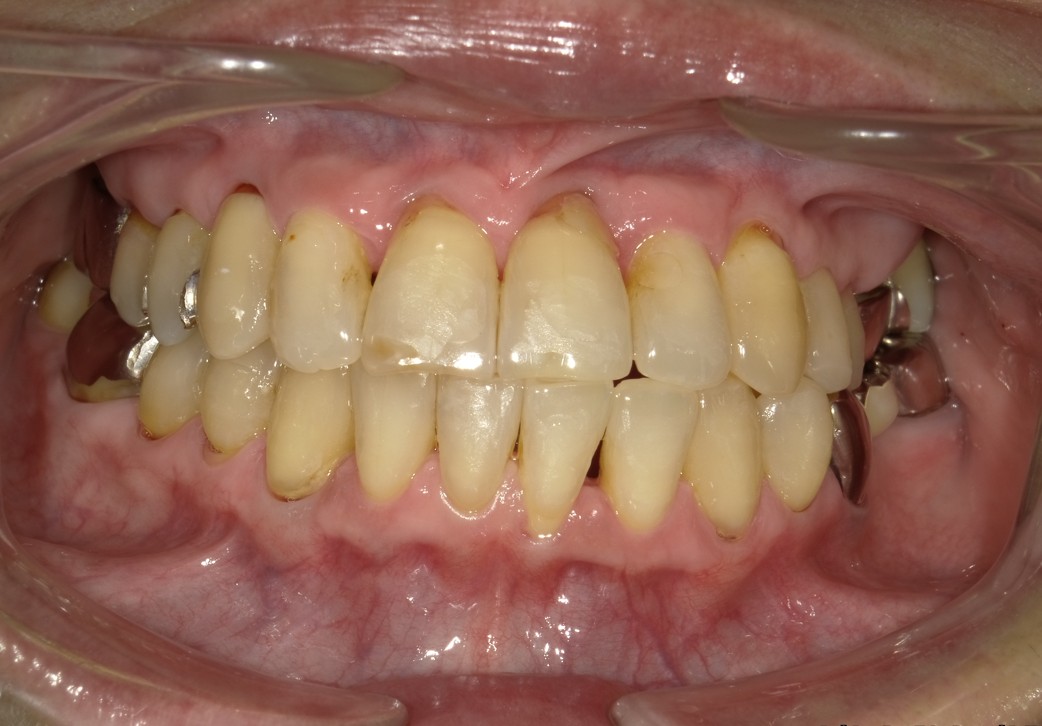

上下のガチャ歯を改善した1症例

治療後 ![]() |

全顎アライナー矯正(クリアコレクト) |

アライナーのみでは改善が難しい部分があったためワイヤー矯正に変更し修正 |

12ヶ月 |